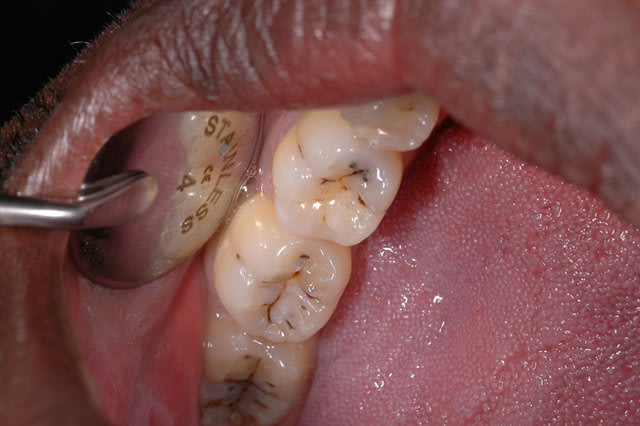

Il ne devrait pas t'avoir échappé que les colorations que nous avons par transparence sous les sillons, montrent une atteinte de la dentine.

Ce que le sondage confirme. Mais c'est vrai que souvent, ces variations de couleurs, quand il s'agit de caries de relative petite étendue, peuvent passer à la trappe d'un manque de lumière et de grossissement. D'ou l'intérêt d'aides optiques, j'utilise des loupes x4,5 et d'une lumière froide très puissante, associée.

Ce qu'a confirmé aussi, l'ouverture des sillons. J'aurais dû, il est vrai prendre une image avant l'éviction des zones cariées.